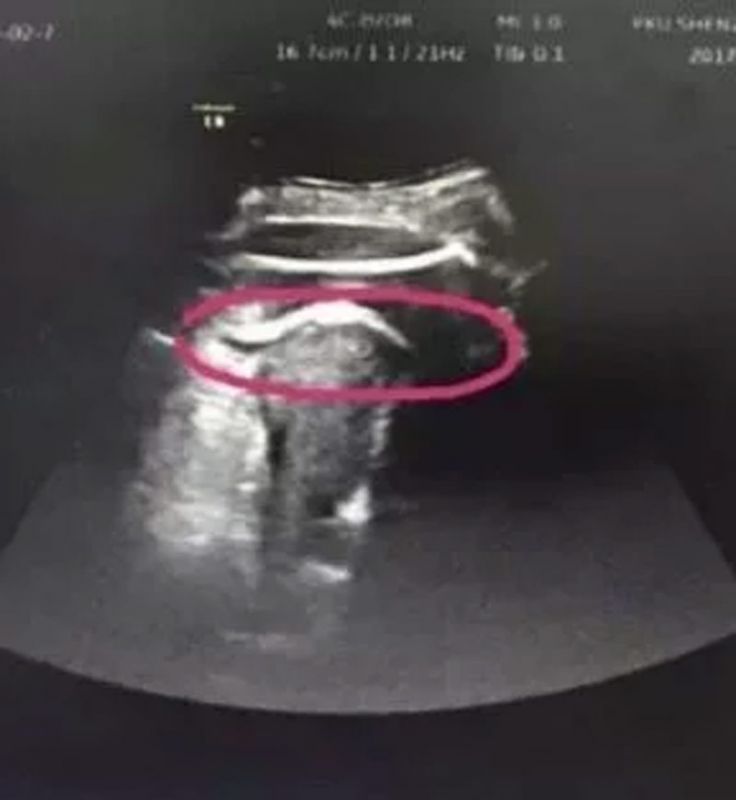

Zhang, como fue identificada, se quejaba de abundante dolor en el estómago, y tenía descontrolados el pulso y la tensión. Los médicos sin sospechar nada, creyeron que se encontraban ante una labor de parto normal, con una rotura uterina, pero cuando realizaron un ultrasonido, se encontraron con una enorme abertura en la cavidad abdominal.

La niña había rasgado el útero y se había quedado atascada por los glúteos.